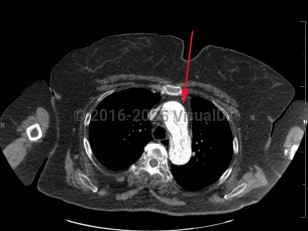

Imaging Studies image of Aortic dissection - imageId=8357567. Click to open in gallery.  caption: '<span>Axial image from CT scan of the chest demonstrating dissection of the thoracic aorta. This is a type A dissection involving the ascending and descending thoracic aorta.</span>'

Axial image from CT scan of the chest demonstrating dissection of the thoracic aorta. This is a type A dissection involving the ascending and descending thoracic aorta.